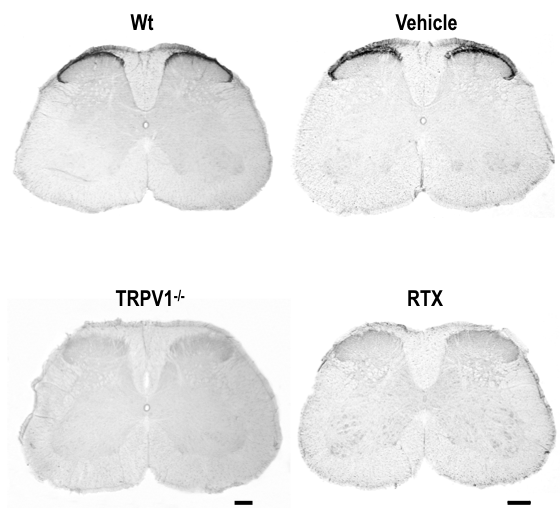

TRPV1 in spinal dorsal horn!!??

Pre-synaptic TRPV1 function proposed in J.Neurosci 2009

Post-synaptic TRPV1 function proposed in Neuron 2012